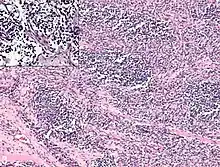

Rhabdomyosarcoma is often difficult to diagnose due to its similarities to other cancers and varying levels of differentiation. It is loosely classified as one of the small-blue-round-cell tumors due to its appearance on an H&E stain. Other cancers that share this classification include neuroblastoma, Ewing sarcoma, and lymphoma, and a diagnosis of RMS requires confident elimination of these morphologically similar diseases.[15] The defining diagnostic trait for RMS is confirmation of malignant skeletal muscle differentiation with myogenesis (presenting as a plump, pink cytoplasm) under light microscopy.[5] Cross striations may or may not be present. Accurate diagnosis is usually accomplished through immunohistochemical staining for muscle-specific proteins such as myogenin, muscle-specific actin, desmin, D-myosin, and myoD1.[26][35][36] Myogenin, in particular, has been shown to be highly specific to RMS,[37] although the diagnostic significance of each protein marker may vary depending on the type and location of the malignant cells. The alveolar type of RMS tends to have stronger muscle-specific protein staining. Electron microscopy may also aid in diagnosis, with the presence of actin and myosin or Z bands pointing to a positive diagnosis of RMS.[5][35] Classification into types and subtypes is accomplished through further analysis of cellular morphology (alveolar spacings, presence of cambium layer, aneuploidy, etc.) as well as genetic sequencing of tumor cells. Some genetic markers, such as the PAX3-FKHR fusion gene expression in alveolar RMS, can aid in diagnosis. Open biopsy is usually required to obtain sufficient tissue for accurate diagnosis. All findings must be considered in context, as no one trait is a definitive indicator for RMS.